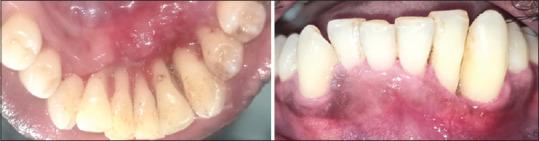

Fibrosarcoma is a rare malignancy of fibroblasts that seldom occurs in the oral cavity. Although rare, fibrosarcoma is an aggressive lesion associated with a poor survival rate. The occurrence of such a highly aggressive lesion on the gingiva is a diagnostic challenge for the clinician. This is because the gingiva is a common site for various inflammatory and nonspecific enlargements, which are commonly benign and the chances to overlook aggressive lesions are high. This case report describes an atypical case of fibrosarcoma of gingiva in a middle-aged individual that mimicked a nonspecific gingival enlargement.

纤维肉瘤是一种罕见的成纤维细胞恶性肿瘤,很少发生于口腔。尽管罕见,但纤维肉瘤是一种侵袭性病变,生存率较低。牙龈出现这种高度侵袭性病变对临床医生来说是一个诊断挑战。这是因为牙龈是各种炎症和非特异性增生的常见部位,这些通常是良性的,因而忽视侵袭性病变的可能性很大。本病例报告描述了一名中年个体牙龈纤维肉瘤的非典型病例,该病例酷似非特异性牙龈增生。